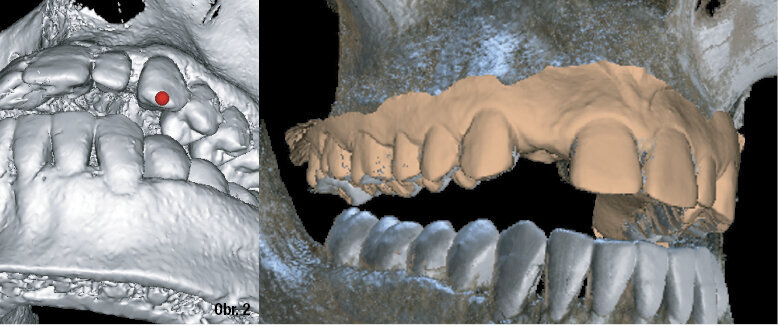

Obr. 2: Zkombinování CBCT a dat z intraorálních skenů usnadňuje podrobné, přesné předoperační plánování